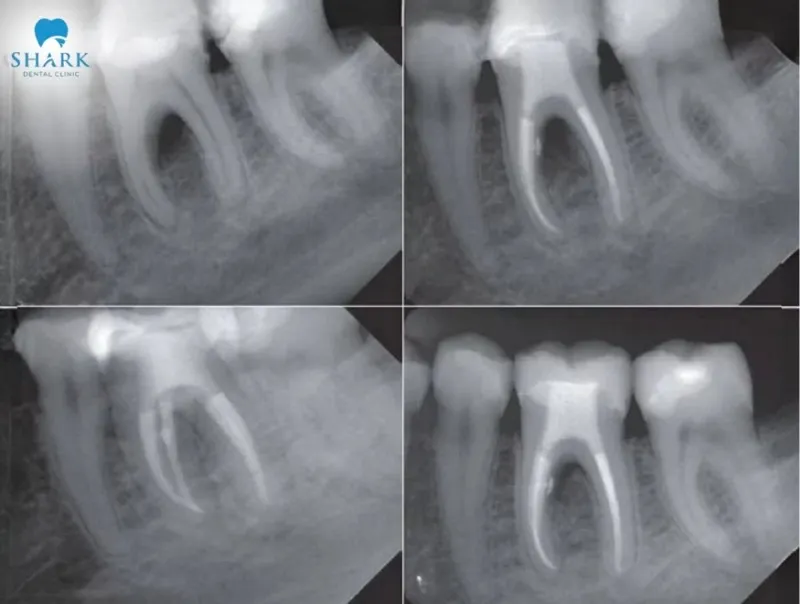

Dead tooth root canal before and After images

Below are some images showcasing the results of dead tooth root canal treatments for your reference.

Typically, the procedure involves cleaning and shaping the root canal system before sealing it tightly. This process helps maintain the natural tooth and restore comfortable chewing function.

Following root canal treatment, the necrotic pulp tissue will be removed. The dentist will clean, shape, and seal the canal to preserve and restore the functionality of the natural tooth. You may experience some sensitivity or mild pain when touching the tooth, often caused by a wide root apex or stimulation from the filling material. However, these symptoms typically resolve within 4–5 days, so there is no need for concern.